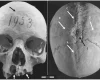

Были удивительно успешными: неолитические люди часто выживали после рискованных операций

4500 лет назад женщине провели две сложные операции на голове: пациентка выжила (фото)

Первая трепанация в истории. Найдены останки женщины из Средневековья с отверстиями в черепе

Выгоняли демонов из головы: ученые выяснили, зачем инки проводили трепанацию черепа